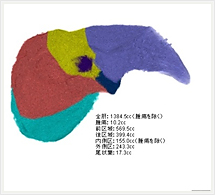

画像紹介

CTでは輪切り像の他にも立体的な画像(3D画像)を作成することもできます。そのためにはより細かくキレイな画像を撮影しなければなりません。当院では64列CTを導入しており、キレイな画像をより細かく撮影することができます。その画像を元に3D画像を作成することによって、より正確な手術のシミュレーションが可能になります。実際に手術をしたときの様子が、手術をする前に画像として見らます。外科系の手術には欠かせない技術となっておりますが、内科系でも血管内手術にも多く利用されております。

当診療放射線技術科では毎日各診療科に対して、その手術に最適な3D画像を提供しております。

以下にその3D画像を一部分紹介します。

頭部